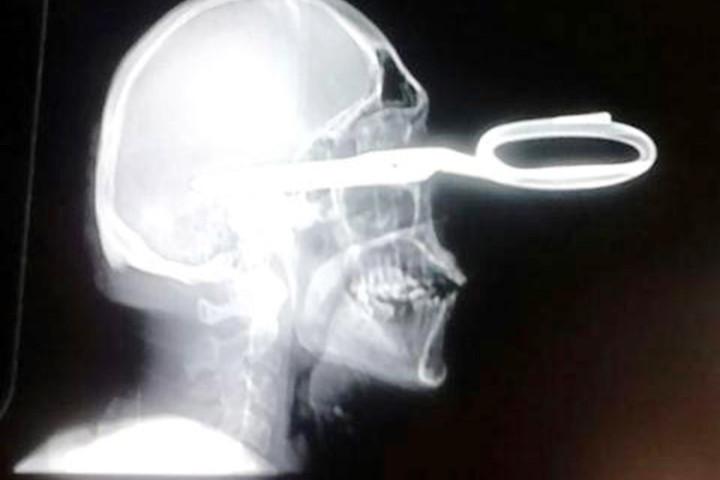

Voici des radiographies impressionnantes de la tête de M. Monroy :

CHIHUAHUA – Le gérant d’un bar au Mexique s’étant fait planter une paire de ciseaux dans la tête, s’est rendu aux urgences d’un hôpital et a expliqué très sereinement et poliment avoir un léger problème, avant d’être pris en charge par les médecins…

En effet, M. Armendariz a commencé à hausser le ton pour une raison inconnue et a sorti une paire de ciseaux de sa poche. M. Monroy lui a alors proposé un verre gratuit pour qu’il se calme, mais rien n’y a fait… M. Armendariz lui a planté les ciseaux en pleine tête et a pris la fuite.

Son ami présent aux moments des faits l’a alors conduit à l’hôpital le plus proche, où une fois sur place le gérant du bar s’est présenté à l’accueil en expliquant « avoir un petit problème et savoir si la réceptionniste pouvait l’aider ». Il a ensuite été pris en charge par les médecins qui ont heureusement pu le guérir, précise l’information parue sur le site du NY Post.

Son surprenant sang-froid et sa politesse compte tenu des circonstances lui ont valu d’être surnommé « El caballero » (« le chevalier » en français) par l’équipe médicale de l’hôpital, qui a expliqué que l’homme avait été très chanceux !